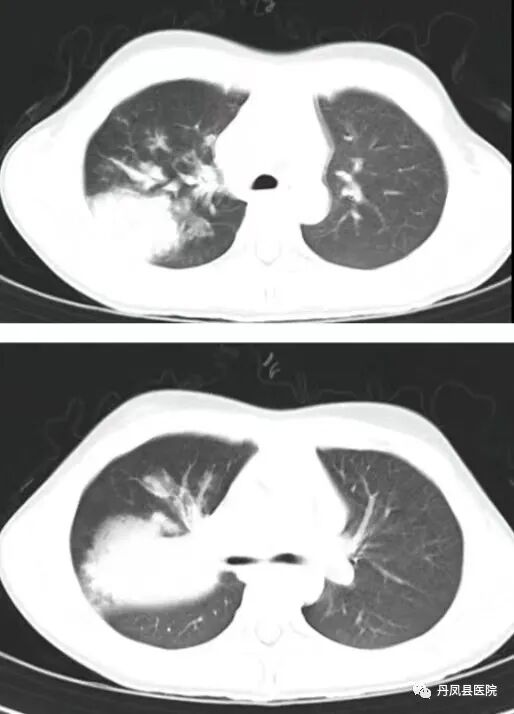

患儿女,8岁。因"发热、咳嗽、皮疹4天"于2023年08月10日入院,患儿病程中反复发热,最高体温39.0℃,伴阵发性咳嗽,夜间为甚,后全身出现淡红色皮疹,感瘙痒不适,可自行缓解,当地诊所给予口服药物及输液治疗3天无效,体温仍反复升高,咳嗽较前增多,且皮疹反复,来我院。入院查体:T39.1℃,P118次/分,R32次/分,W23kg。神志清楚,精神、反应差。颜面部及双耳皮肤可见淡红色大小不等皮疹,伴瘙痒,按压可褪色。双耳垂肿胀,浅表淋巴结未触及肿大,咽部广泛充血,双侧扁桃体 I °肿大,双肺呼吸音粗糙,双肺可闻及细小湿啰音。心律齐,心音有力,腹软,无压痛,神经系统查体无异常。辅助检查:血常规示:WBC5.32×109/L, L47.6%, M6.0%,N44.4%,RBC4.06×1012/L,HGB115g/ L ,PLT288×109/L 。肝肾功、血糖、电解质、心肌酶大致正常。支原体IgM抗体:阳性;血沉26mm/h。降钙素原0.06ng/ml 。凝血系列示:D ﹣二聚体2.19ng/ ml ,余项正常。痰培养:阴性;心电图:正常。胸部 CT 示:右肺上叶及下叶背段感染性病变,右肺上叶前段实变。入院诊断:支气管肺炎;肺炎支原体感染;感染性荨麻疹。诊疗经过及转归:入院后予阿奇霉素抗感染、低分子肝素钙抗凝、地塞米松、葡萄糖酸钙、维生素 C 抗过敏,布地奈德,特布他林雾化吸入等对症治疗。入院后治疗2天体温降至正常、咳嗽减轻,治疗3天皮疹完全消退。8.17复查凝血结果正常。8.20复查胸部 CT 示:与本院2023.8.10CT对比:右肺上叶感染性病变较前吸收好转:上叶前段实变范围较前局限。![]()

![]()

治疗前后胸部CT对比病例三